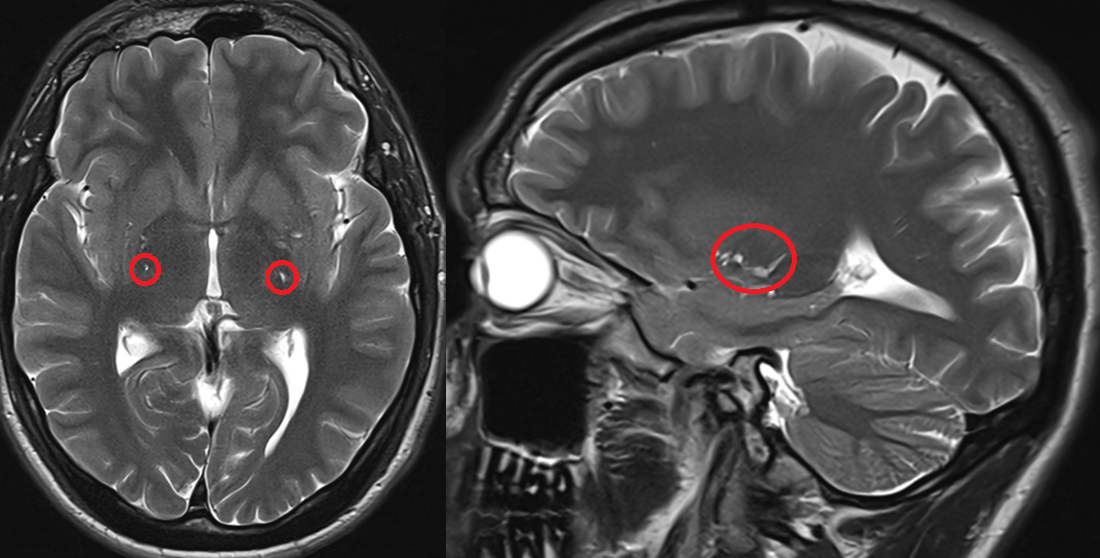

Czy jest ktoś w stanie mi wytlumaczyc dlaczego nagle mogla mi sie zacząć trzęść szyja i kark? Za każdym razem jak napne kark przykładowo przy ruszaniu głową albo gdy np. robie planka albo probuje sie na drążku podciągnąć, czy zwyczajnie zmienić pozycje na krześle to czuje jak mi zaczyna drżeć cały kark jak galareta i za tym idzie głowa. Nigdy wcześniej tak nie miałem, a trwa to już z 2 miesiące i